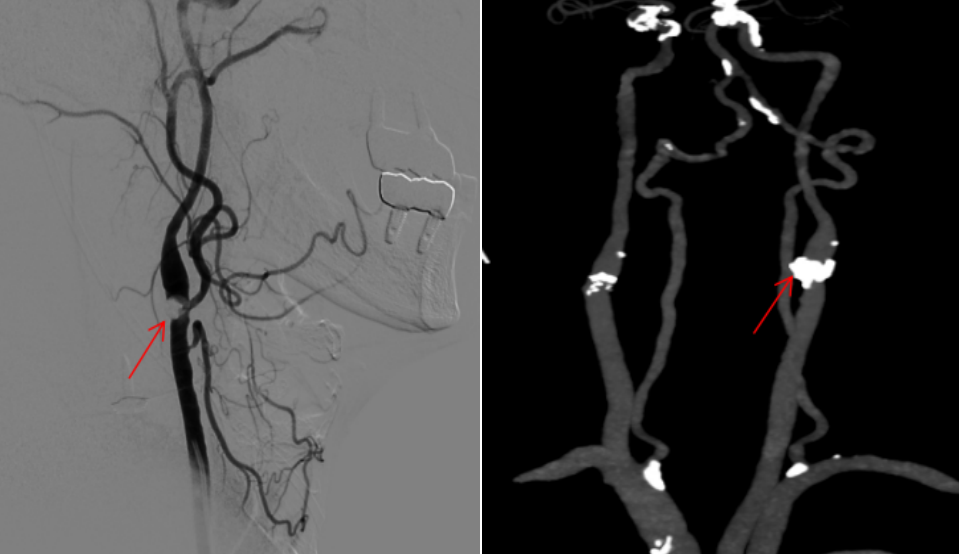

经头颅 CTA、全脑血管造影等检查,发现刘大爷左侧颈动脉窦部出现严重环形钙化斑块,已造成血管重度狭窄,导致同侧大脑供血严重不足,只能依靠对侧颈内动脉通过前交通动脉向左侧大脑中动脉部分代偿供血。

然而,对于刘大爷而言,常规的支架植入(CAS)并非理想选择。因为他的斑块并非普通的软斑块,而是严重的环形钙化斑块,像一圈硬壳一样紧紧包住血管壁。若采用常规的支架植入手术(CAS),会面临两大难题:球囊成形术存在球囊回收后斑块弹性回缩,支架植入后存在支架打开不全、贴壁不良的风险。

对于斑块负荷大、钙化严重、颈动脉严重迂曲的患者,颈动脉内膜剥脱术(CEA)成为更优的选择。经过全面评估,刘大爷的心肺功能也能够耐受全身麻醉和外科手术,专家团队最终确定颈动脉内膜剥脱术(CEA)。